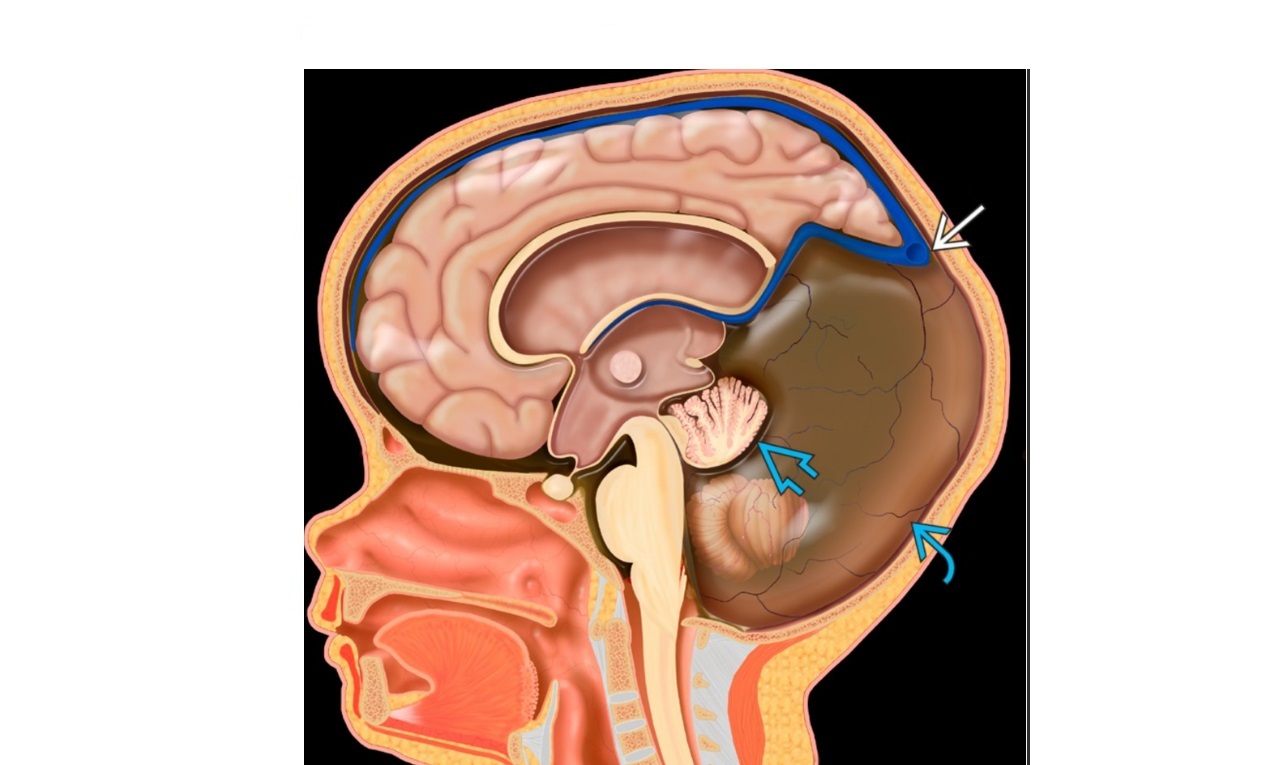

Imaging features of Dandy-walker malformation?

A

Cystic dilatation of the 4th ventricle

Enlarged posterior fossa with elevated tentorium - ‘Torcular-lamboid inversion’

Cerebellar vermis agenesis - superior rotated vermain remnant

Small and widely spaced cerebellar hemispheres

Hydrocephalous